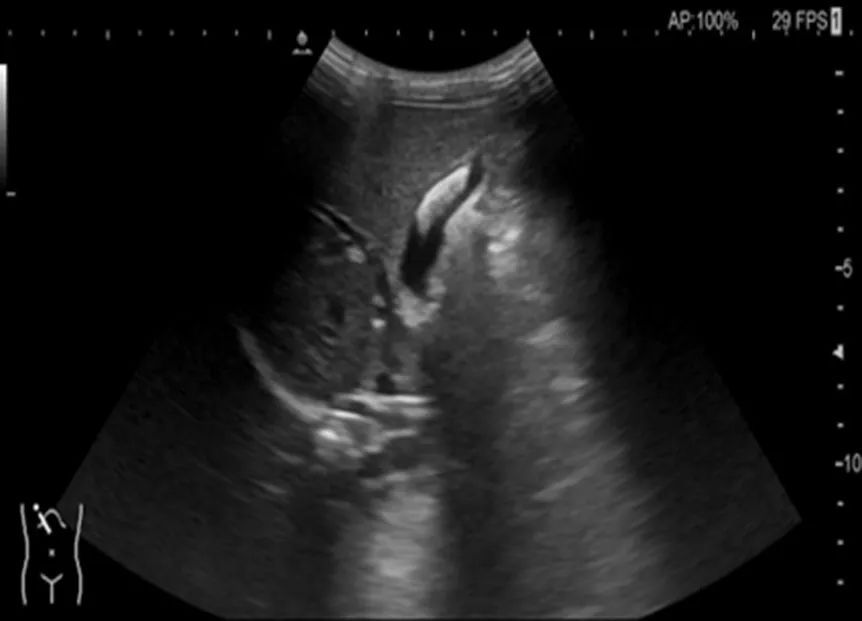

胆囊结石超声声像图

一周后复查,胆囊结石消失